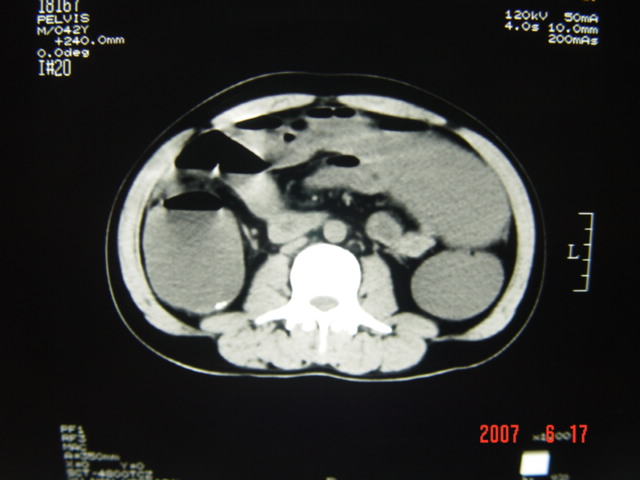

[br][br]以下是引用lkc8963在2007-6-17 13:32:00的发言:[br]完全支持邓主任意见:降/乙交界部占位性病变伴不全梗阻.做个增强或者be可能更好.